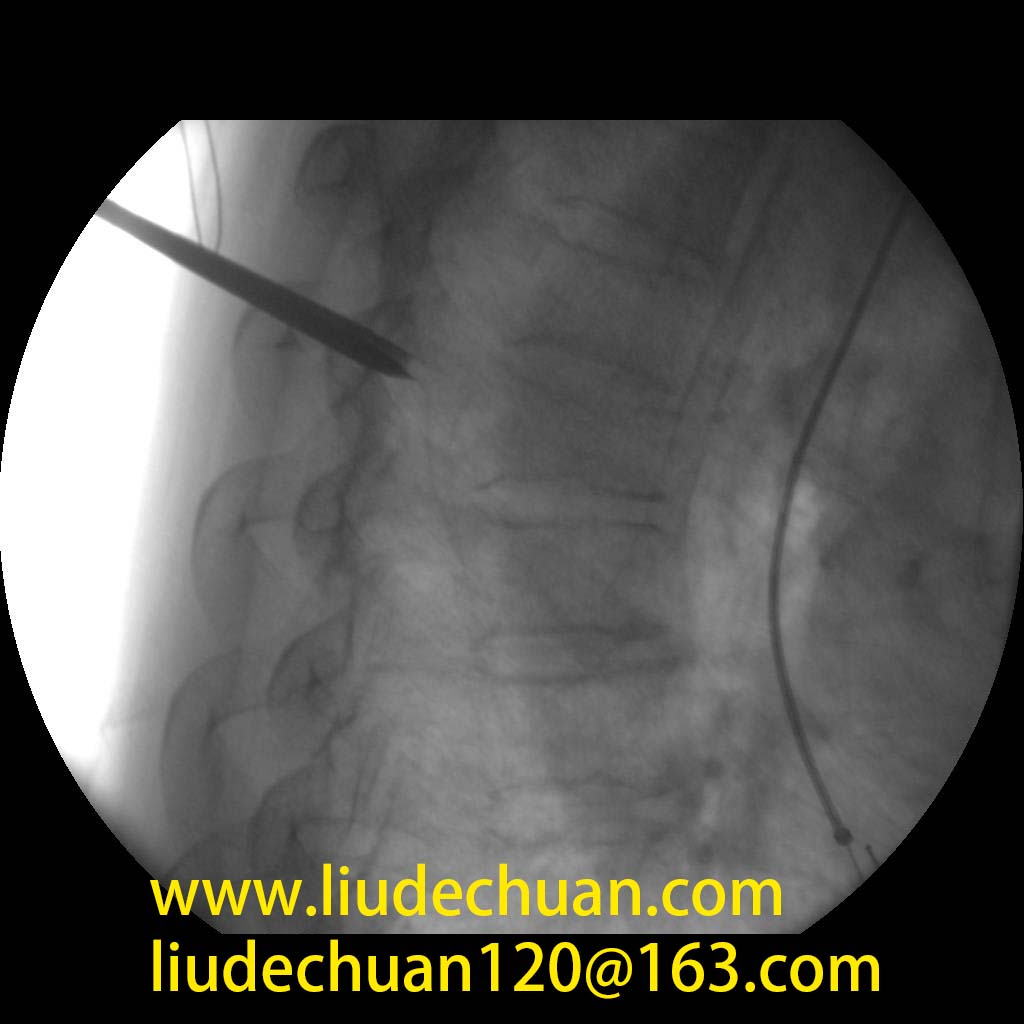

脊柱微创技术

• 经皮椎间孔镜下髓核摘除术

• 单侧双通道内镜(UBE)微创手术

• 微创经椎间孔腰椎融合术

• 球囊扩张椎体成形术(PKP/PVP)